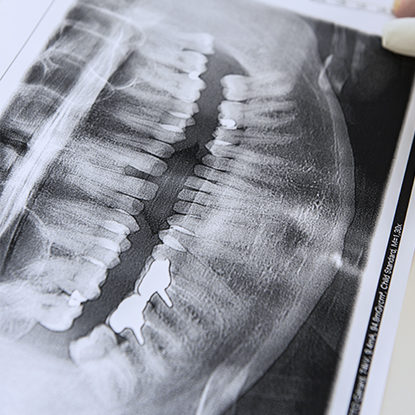

Lors du 2ème RDV de Théo, le Dr Farnier réalise une empreinte, des radios, des photos et, si nécessaire, d’autres examens.